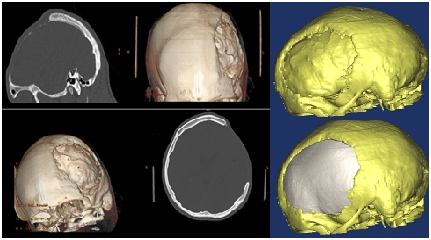

Radi se o devetnaestogodišnjem pacijentu iz Konjica, koji je dvije godine ranije preživio tešku povredu glave iza koje je zaostao veliki defekt svih kostiju lijeve polovine lobanje, uključujući dio baze lobanje i zida očne duplje. Primjenom standarnih metoda u neurohirurgiji i estetskoj hirurgiji nije bilo moguće uraditi vjerodostojnu estetsku i funkcionalnu rekonstrukciju lobanje.

Ponovno se pokazalo da tehnologija i medicina idu rame uz rame. Na osnovu 3D kompjuterizirane tomografije glave napravljen je 3D model lobanje pacijenta, koji je poslužio za formiranje originalnog transplantata.Kalup za transplantat je napravljen na 3D printeru i milimetarski je odgovarao defektu kojeg je trebalo zatvoriti.Sama rekonstrukcija je uspješno realizirana i dobijen je maksimalan estetski i funkcionalni rezultat. U odnosu na ranije rekonstrukcije ova je bila mnogo kompleksnija i tehnički najzahtjevnija, posebno zbog rekonstrukcije bazalnog i prednjeg dijela lobanje, što samo po sebi, značajno produžava trajanje operacije.